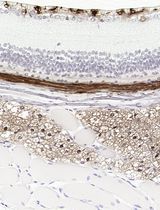

采用 Davidson 固定液和黑色素漂白法优化小鼠眼组织切片的免疫组化染色

Anne Nathalie Longakit [...] Catherine D. Van Raamsdonk

2025年11月20日 1573 阅读